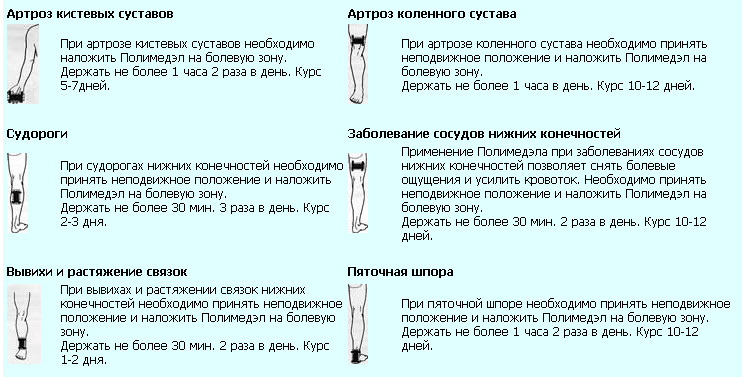

Артроз голеностопного сустава 2 степени схема лечения